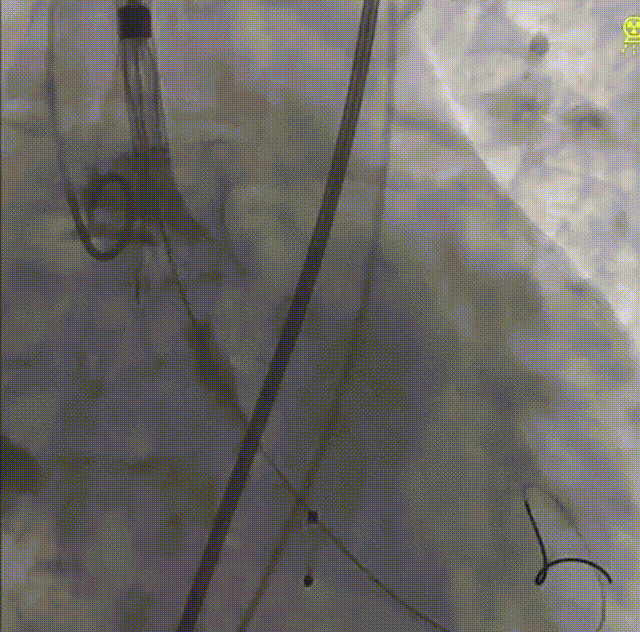

顺利完成CP支架组装后,经股动脉放置鞘管,成功将支架和球囊推送至血管缩窄段进行释放,血管造影结果提示预后效果理想。

术前、术后主动脉造影对比